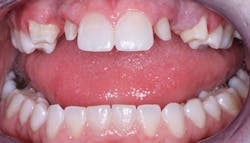

If teeth are impaired esthetically, and the patient has a sincere desire to look more acceptable, the alternatives are bleaching (whitening), crowns, or veneers. If the teeth are acceptable functionally and only defective from an esthetic standpoint, bleaching or veneers are indicated. Bleaching is by far the best and least aggressive choice if that procedure is feasible.

If the lingual or occlusal surfaces are intact, the teeth are anterior teeth, the occlusion is not abusive, and caries is not a major problem, then veneers are the best solution. They can also be the best solution on some premolar teeth that are not in heavy occlusion.

If the teeth are either functionally unacceptable and/or both functionally and esthetically unacceptable, crowns are indicated.

All of the above situations and many more necessitate tooth reshaping and rebuilding to establish adequate occlusal function and esthetics. Crowns are the obvious solution, assuming the patient has the financial resources to have the treatment accomplished (figures 1-3).